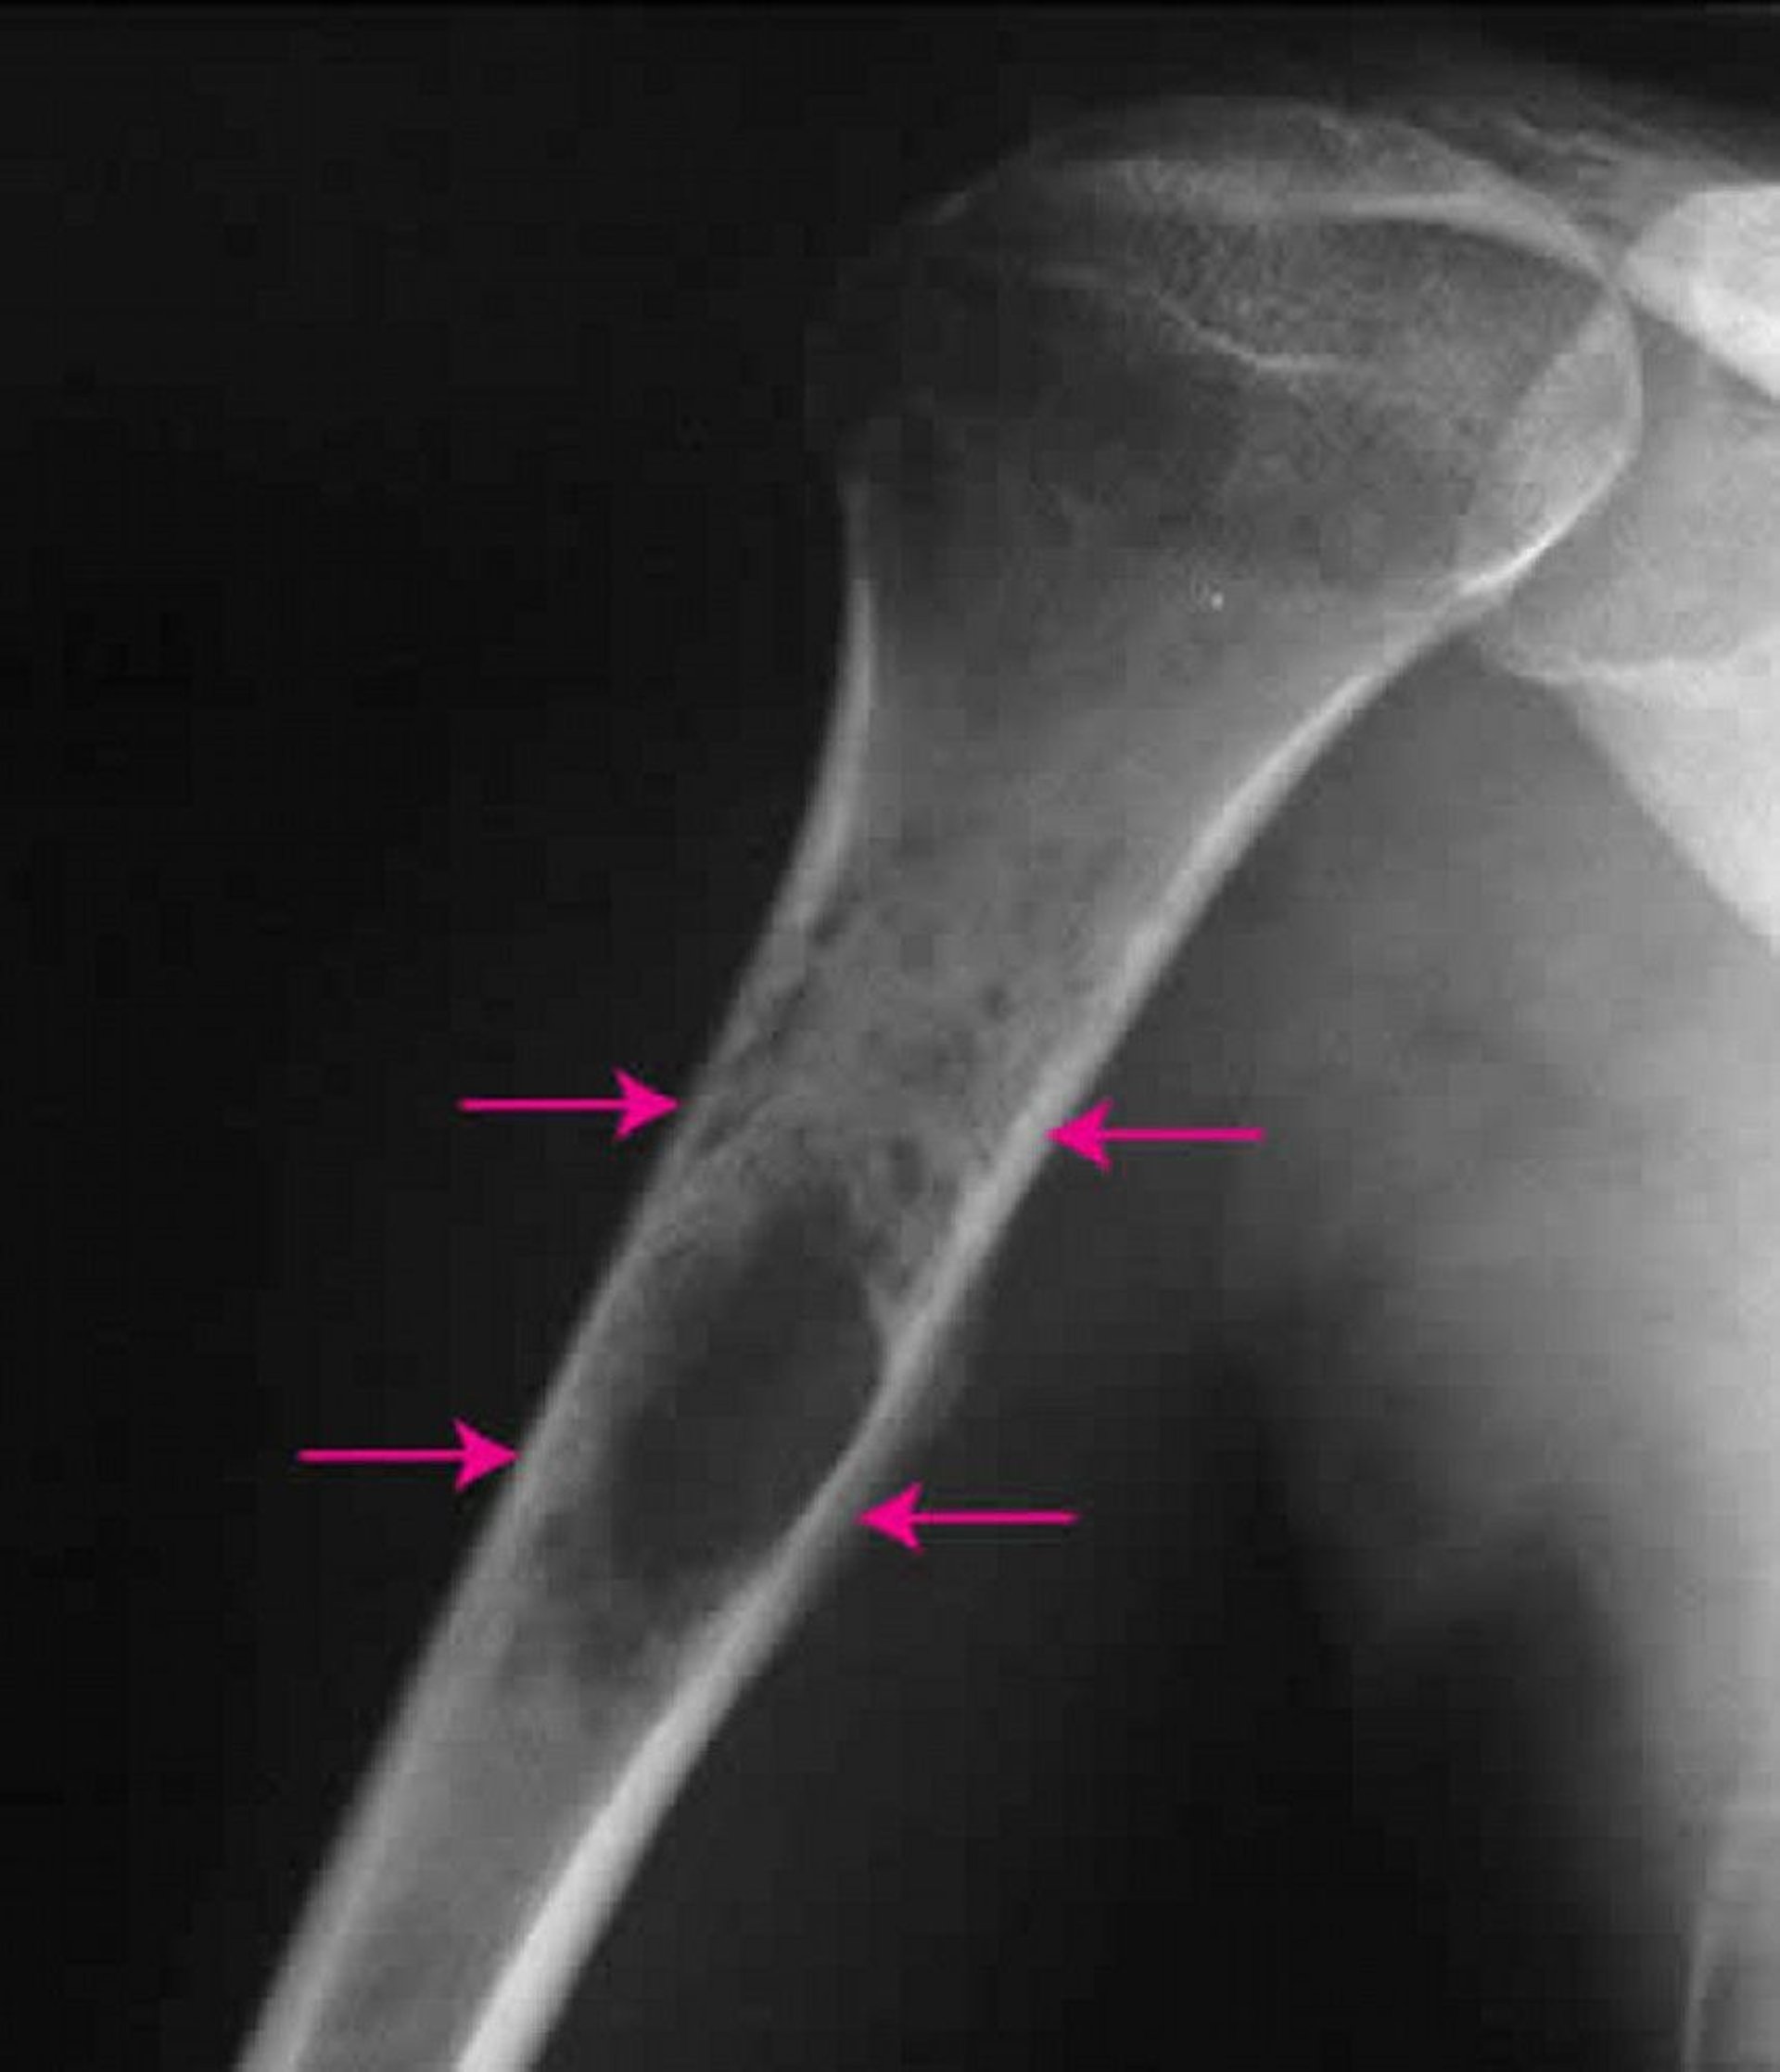

Sarkoma Ewing adalah tumor kanker yang lebih sering memengaruhi pria daripada wanita dan paling sering muncul pada individu berusia 10 hingga 20 tahun. Sebagian besar tumor ini berkembang di lengan atau tungkai, tetapi dapat berkembang di tulang apa pun. Nyeri dan pembengkakan adalah gejala yang paling umum. Tumor ini dapat membesar dan terkadang memengaruhi seluruh panjang tulang. Tumor ini dapat melibatkan sejumlah besar jaringan lunak.

Untuk mendiagnosis sarkoma Ewing, dokter akan melakukan pemeriksaan sinar-x. Meski pemeriksaan sinar-x dapat menunjukkan beberapa detail, pencitraan resonansi magnetik (MRI) dapat membantu menentukan ukuran pasti tumor ini. Untuk mengonfirmasi diagnosis, dokter akan melakukan biopsi.

Pemeriksaan sinar-x pada bahu ini menunjukkan sarkoma Ewing (panah) di dalam tulang lengan bagian atas.

Gambar milik Michael J. Joyce, MD, dan Hakan Ilaslan, MD.